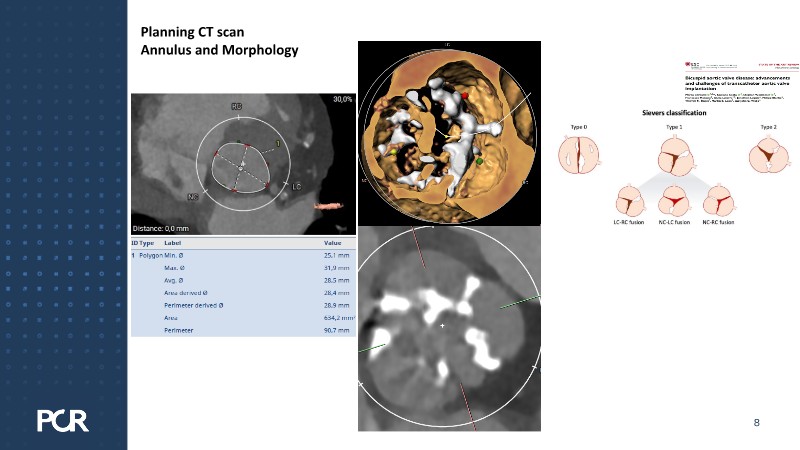

This session examines these crucial aspects through the case of a 77-year-old male with bicuspid aortic valve stenosis, HFpEF and multiple comorbidities, including diabetes, obesity and sleep apnoea.

- To understand why the planning for THV in THV is crucial for every TAVI patient at the time of the first TAVI implantation